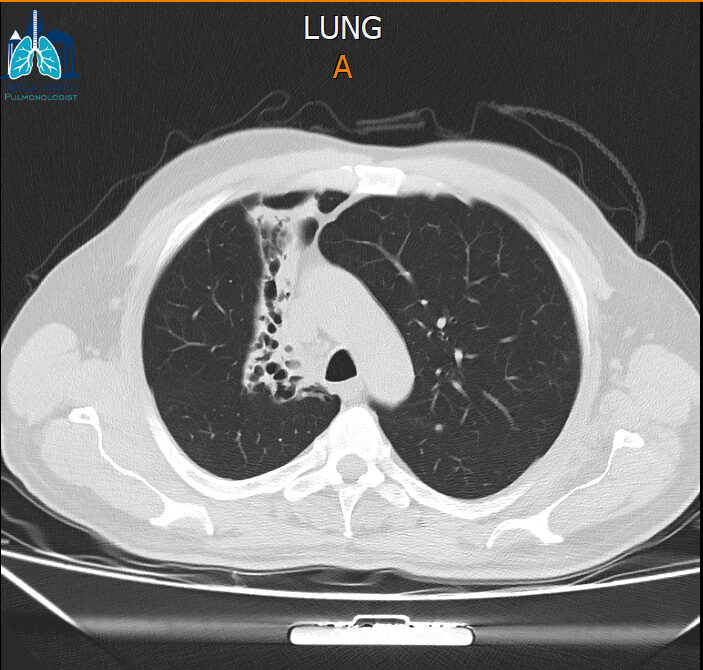

نەخۆشێک کە پێشتر تەنێکی نامۆ لە لوولەی سەرەوەی سییەکانیدا هەبووە، ٣ جار پشکنینی بۆرییەکانی هەناسەی بۆ کراوە و تووشی وەرەمێک بووە، بەڵام دوای ئەنجامدانی پشکنینی بۆرییەکانی هەناسە، بۆمان دەرکەوت کە ئەم تەنە نامۆیە هێلکە بووە.